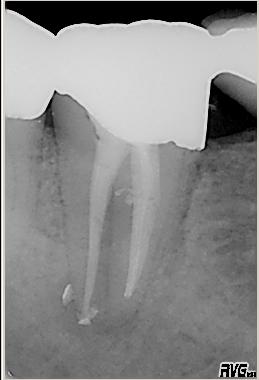

Röntgenmeßaufnahme

Röntgenmeßaufnahme nach vorgängig durchgeführter endometrischer Längenbestimmung. Nach der ersten Behandlung trat zunächst eine Verbesserung der Symptomatik auf. Nach ca. einer Woche kam es zu einer akuten Exacerbation mit lingualer Abszeßbildung. Der Abszeß wurde inzidiert